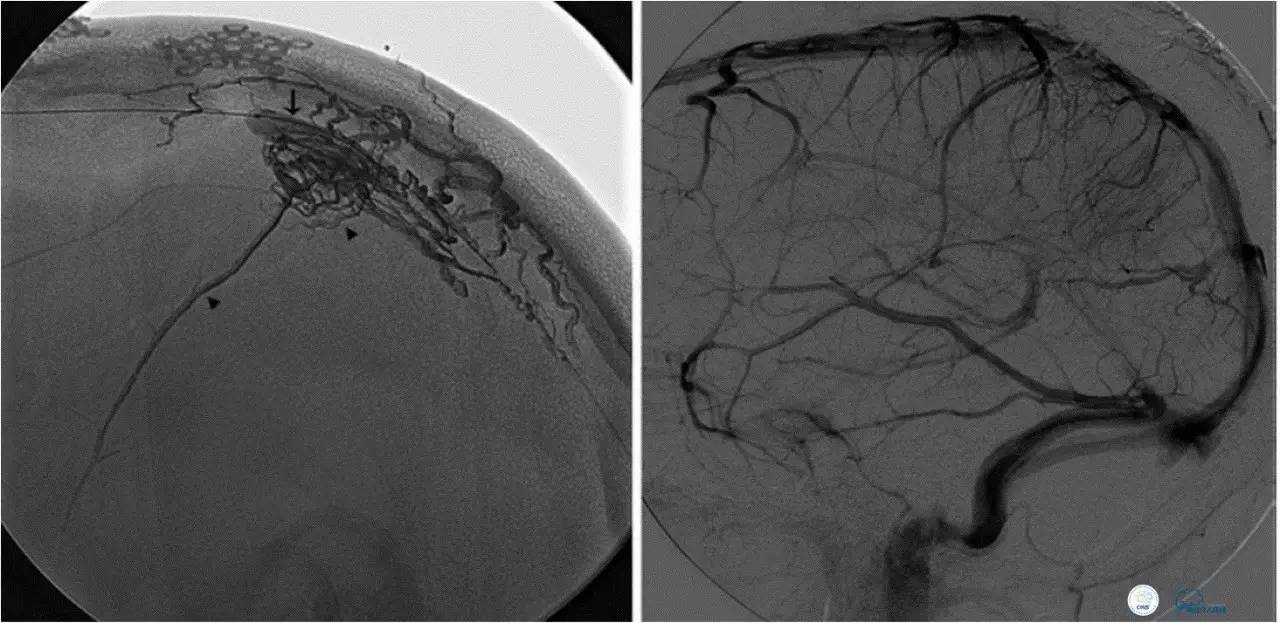

乙状窦区的DAVF,供血动脉细小,静脉引流道通畅。

同侧颈内静脉试图进入引流静脉,但是由于角度问题非常困难。

从对侧颈内静脉绕路进入引流静脉。

Sceptor球囊导管到达静脉内,充盈球囊,让后注入Onyx。

术后造影提示DAVF治愈。

侧窦区DAVF,直接引流入横窦,为保护窦,横窦放入球囊8*80。

最终栓塞结果,窦通畅。

文献中图片,上矢状窦内放置球囊保护。